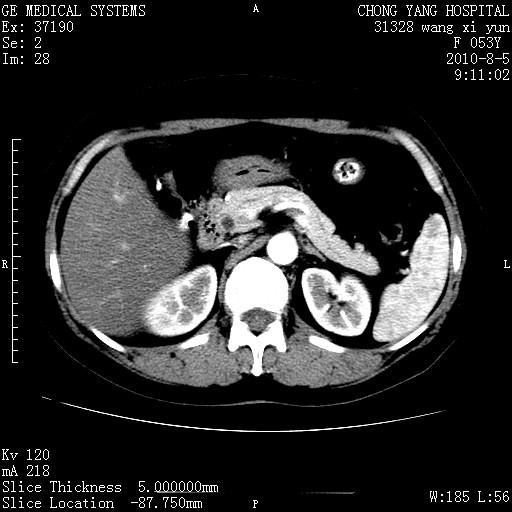

标题: CT28214:F41Y 血尿二十天,建议盆腔平扫加增强。

1)考虑肝左叶胆管细胞癌。2)脂肪肝。